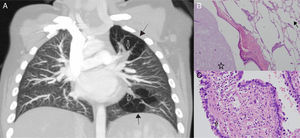

A 2 year-old girl presented with a 6-month history of recurrent airway infections. On anteroposterior chest X-ray, focal radiolucent areas were seen in both the upper zone and paracardiac region of the left lung. On contrast-enhanced chest computed tomography, central mucocele formations were observed in the left perihilar region, together with bi-segmental air trapping and oligaemia, suggestive of bi-segmental bronchial atresia (Fig. 1A). The patient underwent bi-segmentectomy. The histopathology report included mucocele formations and emphysematous changes confirming bronchial atresia, together with respiratory epithelial lined cysts and a thin fibromuscular layer in the cyst wall, suggesting areas of focal congenital pulmonary airway malformation (CPAM) (Fig. 1B).

(A) Contrast-enhanced, coronal plane, chest computed tomography. Closed arrows show mucoceles and black arrows show air-trapped segments. (B) Haematoxylin•eosin, í100 magnification. The air trapping areas (open arrow) and mucocele (asterix), confirming bronchial atresia. (C) Haematoxylin•eosin, í400 magnification. CPAM areas (closed arrow) showed by respiratory epithelial lined cysts and a thin fibromuscular layer in the cyst wall.